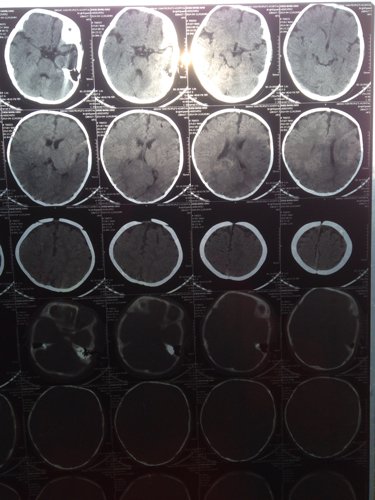

宝宝出生时被诊断为轻度缺血缺氧性脑病,住院治疗一个疗程,现在宝宝5个月复查做了CT,麻烦专业人士给

宝宝出生时被诊断为轻度缺血缺氧性脑病,住院治疗一个疗程,现在宝宝5个月复查做了CT,麻烦专业人士给看看,谢谢

这个大脑缺氧的话CT是检查不出什么问题的,这个需要注意的和观察的